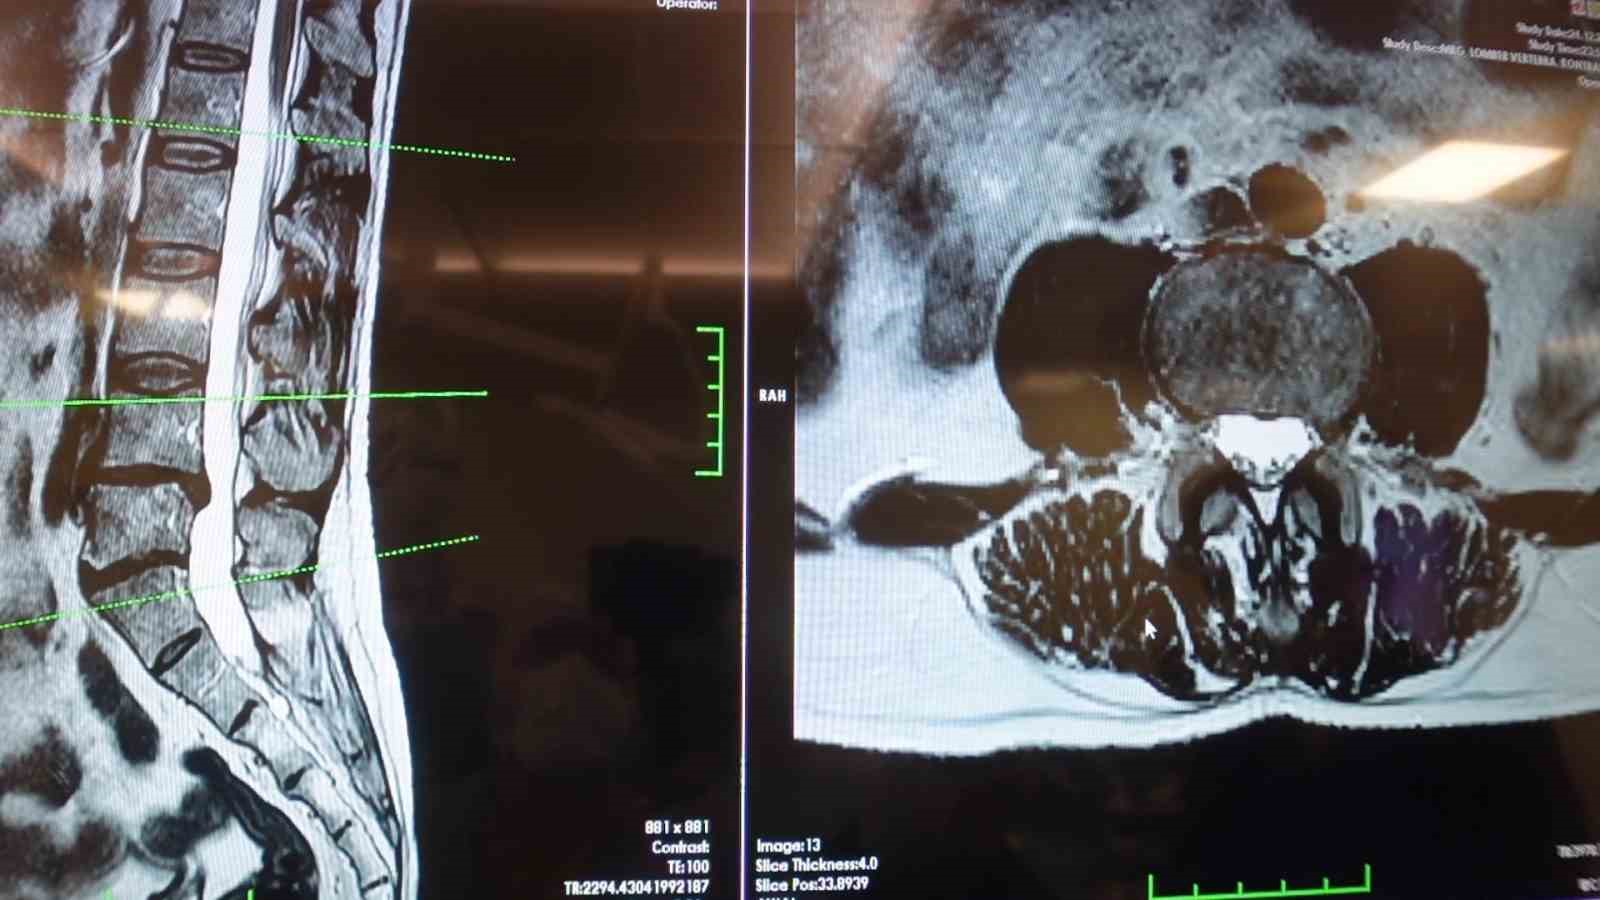

Elazığ Fırat Üniversitesi Hastanesi Beyin ve Sinir Cerrahisi Anabilim Dalı Başkanı Prof. Dr. Fatih Serhat Erol, bel fıtığı hastalığı hakkında açıklamalarda bulundu. Beyin ve sinir cerrahisi pratiğinde sık karşılaşılan hasta gruplarından birinin omurga hastaları olduğunu belirten Prof. Dr. Erol, "Boyun ve sırt omurlarının yanı sıra en çok bel bölgesiyle ilgili sorunlar görülüyor. Bel fıtığı önemli bir hastalıktır. Bel ağrılarının büyük bir kısmının bel fıtığından değil, mekanik bel ağrısından kaynaklanıyor. Mekanik bel ağrısının kaslar, eklemler, iskelet sistemi ve bu yapıları birbirine bağlayan bağların uzun süreli zorlanması sonucu ortaya çıkmaktadır. Bu durumun hastalarda şiddetli bel ağrısına neden olabilir. Mekanik bel ağrısının bel fıtığı ile karıştırılmaması gerekiyor. Bel fıtığına kıyasla mekanik bel ağrıları çok daha sık görülüyor. Bir diğer önemli hasta grubu ise omurilik kanal darlığı olan hastalardır. Bu hastalıkta dejeneratif süreçler sonucunda omurilik kanalında ve sinir köklerinin geçtiği kemik kanallarda daralma ve kireçlenme meydana geliyor. Bu durumun omurilik ve sinir köklerinde sıkışmaya yol açar. Hastaların ayakta dururken ya da yürürken bel, kalça ve bacaklara yayılan şiddetli ağrılar hissettiğini, yürüyüş mesafesi arttıkça oturup dinlenme ihtiyacı duyarlar. Tedavi sürecinin doğru tanıya göre belirleniyor. Bel ve bacak ağrısı şikayeti olan hastaların mutlaka bir beyin ve sinir cerrahisi uzmanına başvurması gerekiyor. Hastaların şikayetlerinin dinlenmesi, gerekli muayene ve tetkiklerin yapılmasının ardından hastalıkların birbirinden ayırt edilebildiğini ve buna uygun tedavi planının oluşturulur" cümlelerini kullandı.